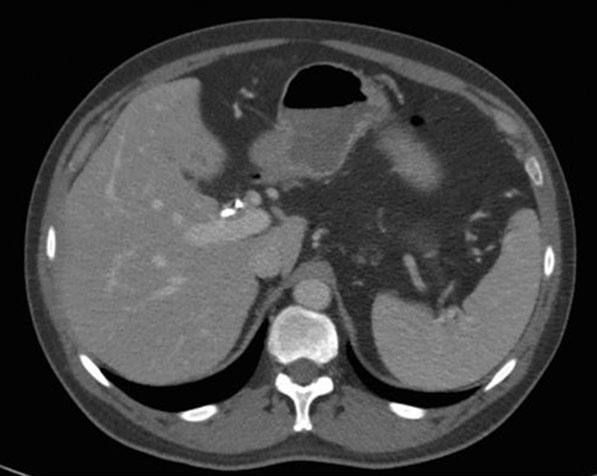

Two days later, he was referred to hepatology clinic for further workup. A trial of empiric prednisone, dosed at 40 mg twice per day, was started on account of concerns for IAC. The pathology results showed reactive epithelia only, without malignancy, and negative for FISH, IgG, and IgG4 stains. He returned to hepatology clinic three weeks later reporting resolution of all of his previous symptoms since initiation of prednisone. All his liver chemistry had improved to normal. The repeat CT scan showed improvement in the mass-like thickening of the CHD, now measuring 9 mm by 4 mm (Figure 4), with improvement in the urothelial thickening and resolution of the hydronephrosis. His prednisone was decreased to 40 mg once a day and thereafter to 30 mg once per day (Figure 5). Three weeks later he continued to be asymptomatic, and a repeat CT scan showed improvement in the mass size, continued CHD wall thickening, and resolution of his biliary ductal dilatation. A repeat EUS and ERCP done three weeks after the scan demonstrated resolution of the hilar mass and marked improvement of the CHD structuring, and the stents were removed. Brushings from the hilum were negative for malignancy. A month later, the patient started complaining of weight gain, muscle aches, and insomnia. The prednisone dose was then tapered to 20 mg per day and mycophenolate mofetil (MMF) 500 mg twice per day was added to his regimen. He continued to remain asymptomatic, liver chemistry tests remained normal, and repeat CT scans showed overall improvement in his CHD wall thickening (Figure 6). He continued to feel well on this regimen and denied any complain.

Figure 6: CT image demonstrating improved, although persistent, bilateral urothelial thickening with stable left hydronephrosis. CT: computed tomography.